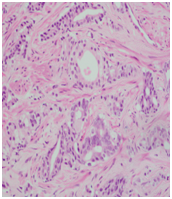

Trans-rectal ultrasound guided biopsy of the prostate confirmed the adenocarcinoma Gleason score 9 (4+5), while the mandibular lesion biopsy revealed metastatic prostate adenocarcinoma (Figures 6–8).

Figure 6 Mandibular biopsy.

Figure 7 & 8 Prostate biopsy.